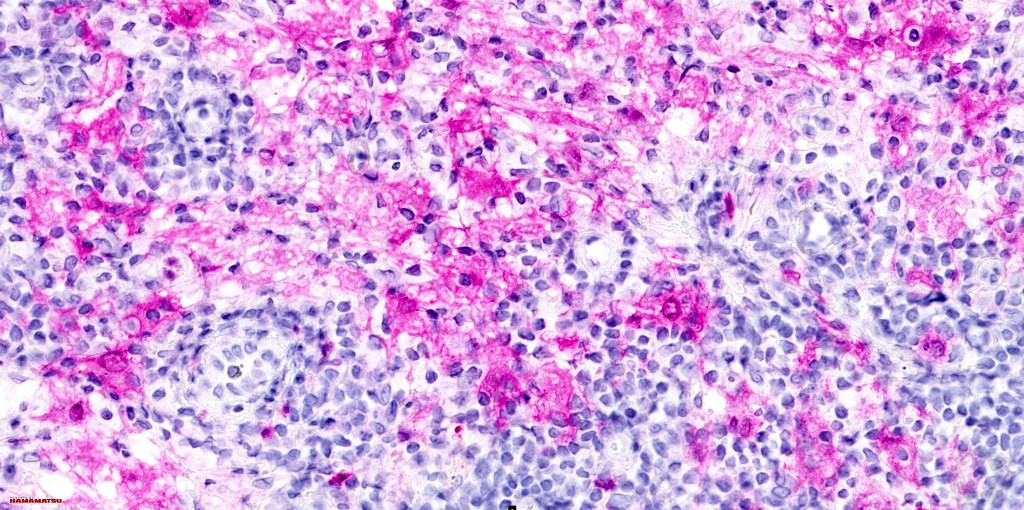

•Emperipolesis of lymphocytes, plasma cells & neutrophils

•Histiocytes are S100, CD68 & CD163 +ve

.CD1a & langerin -ve